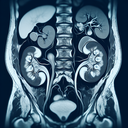

МРТ урографія

МРТ урографія — це неінвазивний метод діагностики сечовидільної системи, що використовує магнітно-резонансний томограф для створення детальних зображень нирок, сечоводів і сечового міхура. ### Переваги МРТ урографії: - **Безпека:** Не використовує іонізуюче випромінювання. - **Якість зображення:** Високоякісні зображення для оцінки анатомії та функції сечовидільної системи...